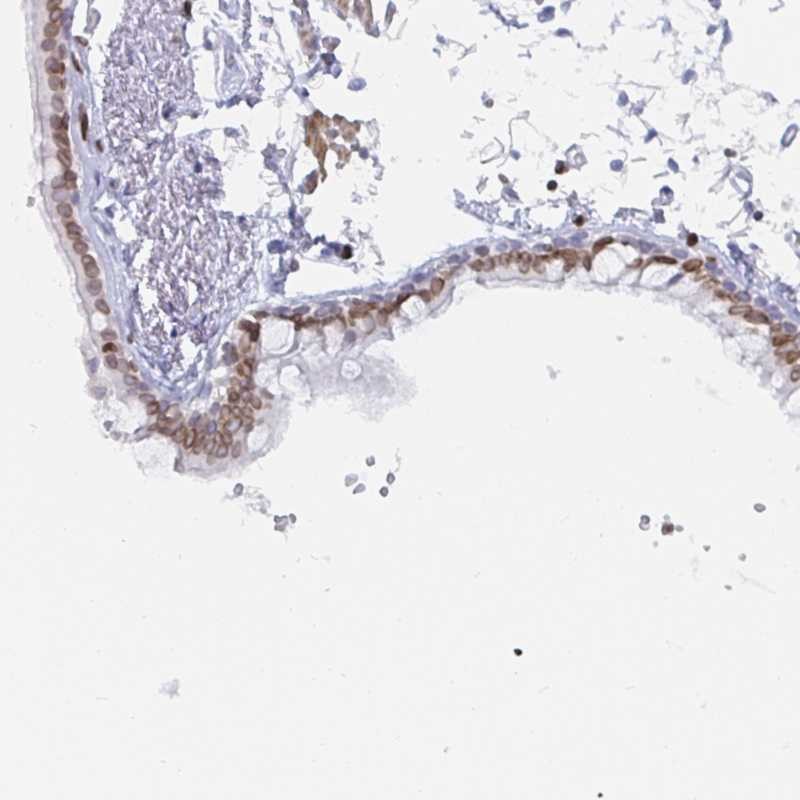

Immunohistochemical staining of human bronchus shows moderate nuclear membranous positivity in respiratory epithelial cells.